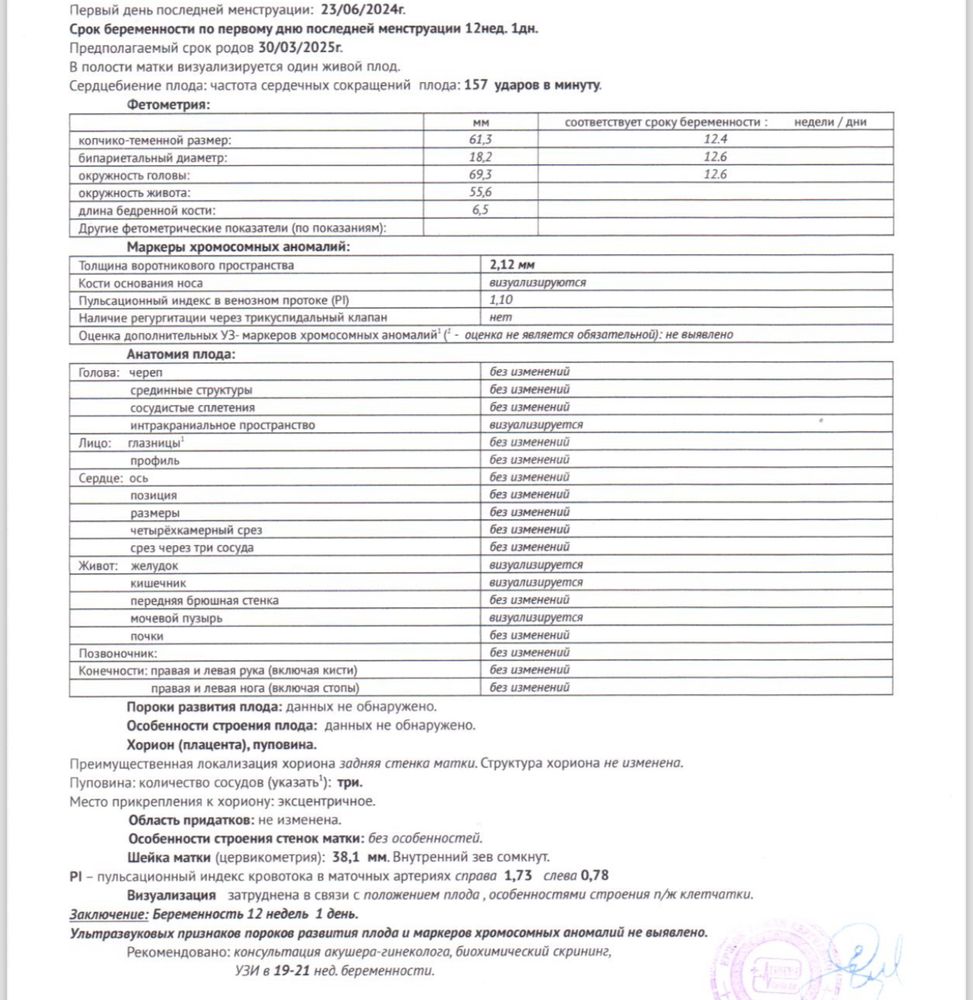

Сегодня прошла УЗИ, все хорошо☺️🙏🏻

Вопрос такой возник, на всех предыдущих узи (последнее в 8+6) мне указывали крепление хориона по передней стенке, а теперь по задней😳 мигрировал? Так бывает да?